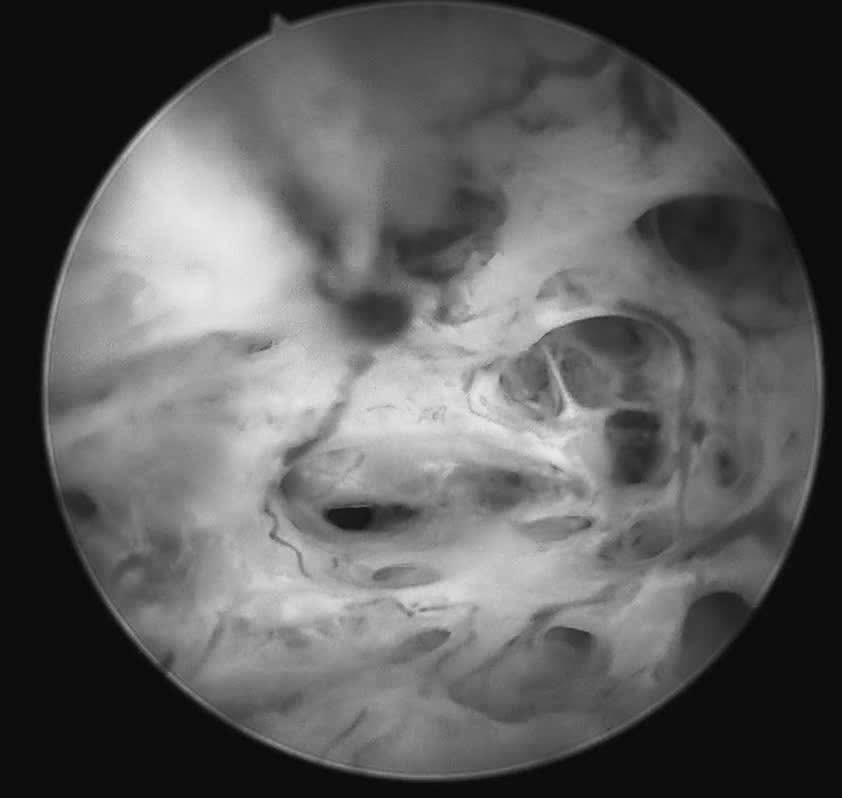

Trước tình huống đó, tại Khoa Khám Phụ khoa Tự nguyện, bệnh nhân được tư vấn thực hiện soi buồng tử cung sinh thiết bằng ống soi nhỏ, một phương pháp cho phép đánh giá trực tiếp buồng tử cung mà không làm tổn thương màng trinh. Ca thủ thuật được ThS.BSCKII Nguyễn Biên Thùy – Trưởng khoa Khám Phụ khoa Tự nguyện trực tiếp thực hiện.

Quá trình soi diễn ra an toàn, nhẹ nhàng. Bệnh nhân hoàn toàn tỉnh táo và có thể quan sát trực tiếp hình ảnh buồng tử cung trên màn hình: niêm mạc nham nhở, tăng sinh không đồng đều, nhiều mạch máu bất thường, những dấu hiệu gợi ý tổn thương ác tính. Mẫu sinh thiết được lấy ngay trong quá trình soi để làm xét nghiệm mô bệnh học.